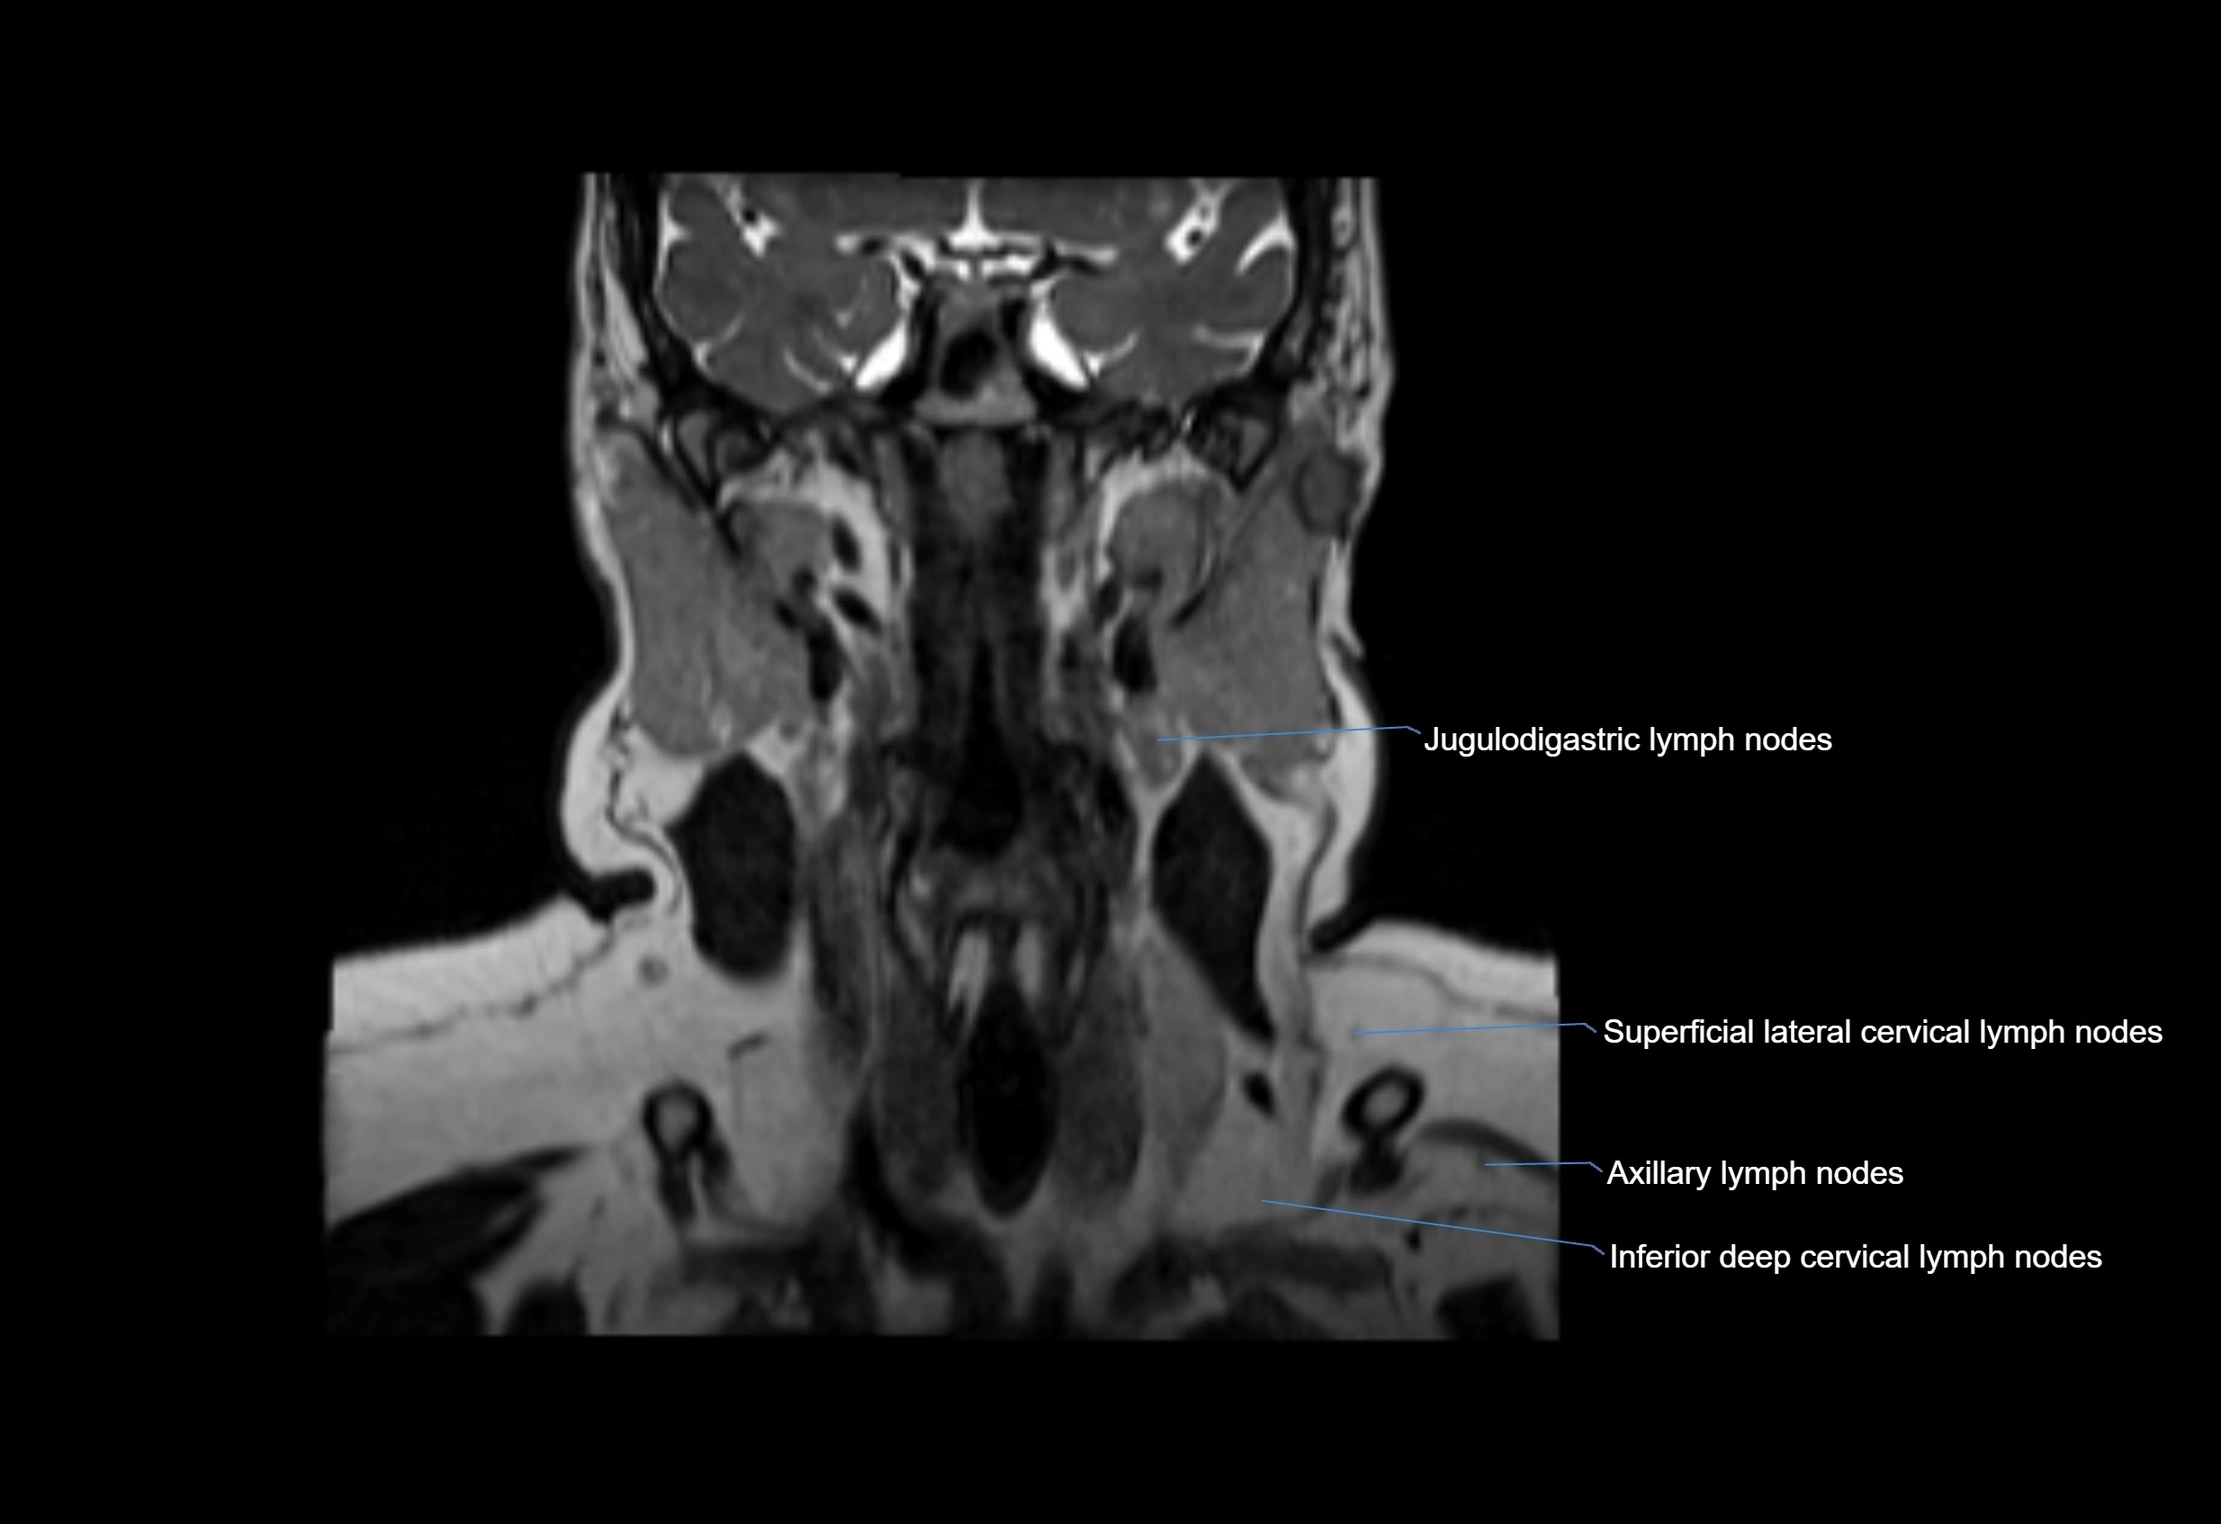

MRI Appearance

T1-weighted images:

• Normal accessory nodes appear as small, oval hypointense to intermediate signal structures within subcutaneous fat

• Surrounded by hyperintense fat, enhancing contrast for visualization

• Pathological nodes may appear enlarged or rounded, sometimes with cortical thickening

T2-weighted images:

• Nodes show intermediate signal, with surrounding fat bright

• Useful for detecting edema, inflammation, or infiltration

• Fatty hilum may appear slightly hyperintense relative to cortex

MRI images

image